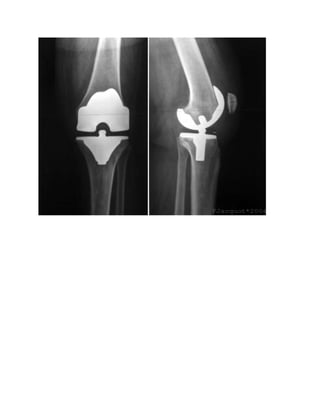

KNEE REPLACEMENT

Due to rise in knee joint osteoarthritis, there is a rise in cases of knee

replacement surgeries. The knee replacement is also known as knee

arthroplasty. It is of two types:

 Partial Knee Replacement.

 Total Knee Replacement(TKR).

During knee joint replacement surgery, damaged cartilage and bone are

removed from the knee joint. Man-made (artificial) pieces, called

prostheses, are then placed in the knee.

These pieces may be placed in up to three surfaces in the knee joint:

 Lower end of the thigh bone. This bone is called the femur. The

replacement part is usually made of metal.

 Upper end of the shin bone--the large bone in your lower leg. This

bone is called the tibia. The replacement part is usually made from

metal and a strong plastic.

 Back side of your kneecap. Your kneecap is called the patella. The

replacement part is usually made from a strong plastic.